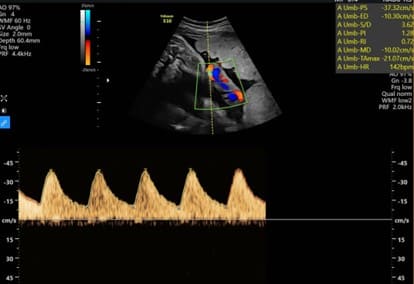

Là kĩ thuật siêu âm đường bụng sử dụng đầu dò 2D để đánh giá các giá trị sinh trắc của thai như: chiều dài đầu mông, đường kính lưỡng đỉnh, chu vi đầu, chu vi bụng, chiều dài xương đùi; từ đó ước lượng được trọng lương thai nhi, đánh giá tình trạng phát triển của thai so với tuần tuổi có bình thường không. Đồng thời đánh giá tình trạng tim thai, tình trạng bánh rau, ối cũng như các tổn thương khác mà siêu âm 2D – Doppler màu quan sát được, như tình trạng động mạch tử cung, động mạch não giữa, ống tĩnh mạch…

Đây là kĩ thuật thường được sử dụng khi thai được khoảng 10 tuần tuổi, khi đó kích thước thai tương đối lớn, có thể dễ dàng quan sát qua đường bụng. Đặc biệt trong những tuần cuối của thai kỳ, đây là kĩ thuật đầu tay để đánh giá tình trạng thai nhi trước khi chuyển dạ, vì lúc này thai đã quá to, không thể sử dụng siêu âm thai 4D-5D hoặc siêu âm đầu dò âm đạo. Trong những tuần cuối, bác sĩ sẽ siêu âm thai để ước lượng cận nặng, tiên lượng đẻ thường hay đẻ mổ, ngoài ra còn quan sát tình trạng dây rốn như quấn cổ, thắt nút…; tình trạng bánh rau như: vị trí bám, có tụ máu hay bong rau không…; tình trạng nước ối: thiểu ôi, bình thường hay đa ối.

Siêu âm thai 2D – Doppler màu có thể đánh giá tình trạng dây rốn